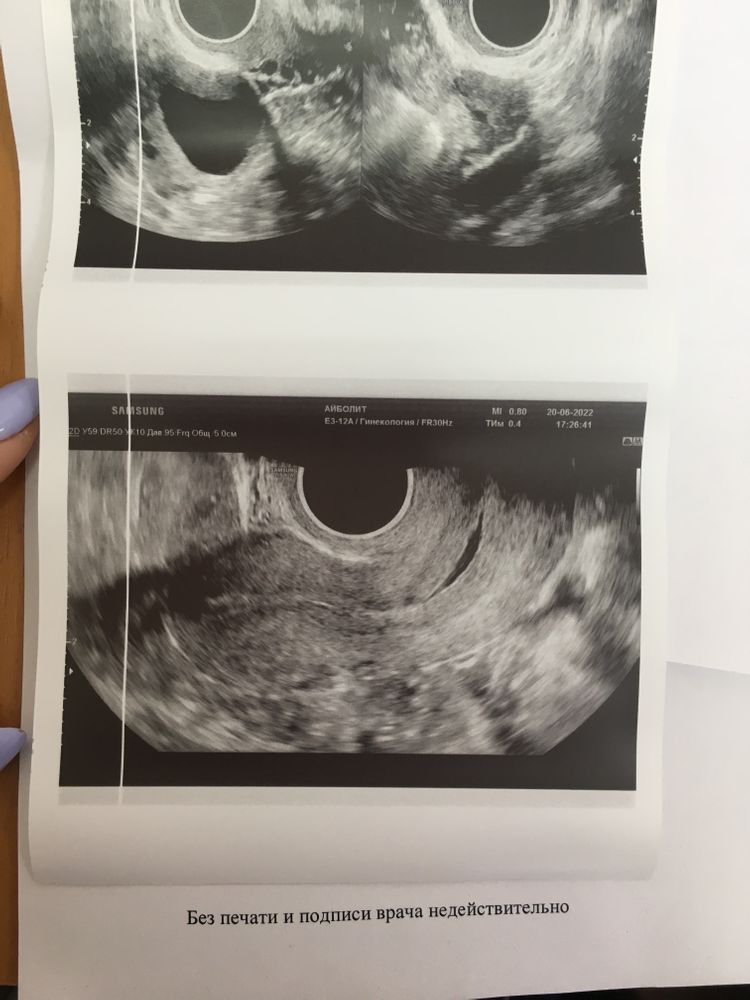

В итоге сходила вчера на УЗИ и толком ничего не поняла, врач не пояснила. Сказала что не может понять, как будто должна скоро начаться овуляция но при этом эндометрий маленький. Также поставила под вопросом МФЯ. Сказал сделать ещё раза фолликулометрию и иди к гинекологу с результатами.

Девочки посмотрите пожалуйста мои анализы и результаты УЗИ. Может вы что-то поймёте и мне объясните. Не могу ни как себя успокоить, переживаю. Даже работать не получается(